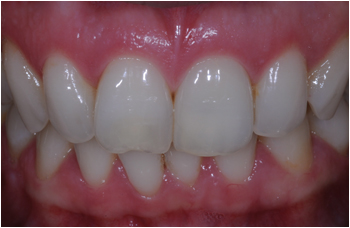

After

Great result after whitening